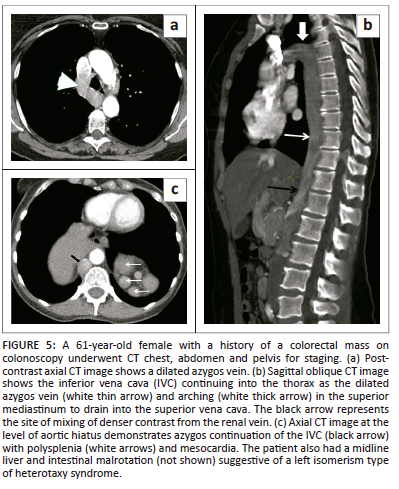

Interruption of the inferior vena cava with azygos or hemiazygos continuation

Absence of the hepatic segment of the IVC is thought to be because of failure of the right subcardinal-hepatic anastomosis with resultant right subcardinal vein atrophy and shunting of blood from the supra-subcardinal anastomosis to the azygos vein. The azygos vein joins the superior vena cava at the right paratracheal space in the expected normal location. The hepatic segment is not entirely absent. It drains directly into the right atrium. The right gonadal vein drains to the ipsilateral renal vein as the post-subcardinal anastomosis does not contribute to the formation of the IVC. It has a reported prevalence of 0.6%.1,7,9 Azygos continuation is more common than hemiazygos continuation. Azygos continuation of the IVC can be seen in asymptomatic patients or in association with other congenital abnormalities such as severe congenital heart disease and asplenia or polysplenia syndromes (Figure 5).1,8,23 An enlarged azygos vein can mimic a right paratracheal or retrocrural lymph node. Knowledge of this variation is useful for preoperative planning for cardiopulmonary bypass and vascular procedures.1,9